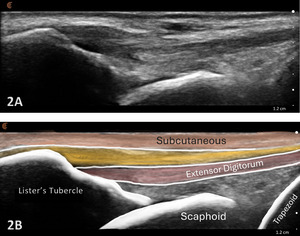

- Transducer Type: Because of the superficial nature of the wrist structures, a standard high-frequency, linear array transducer is normally used. In some instances, the L-shaped, hockey stick-type transducer may be required.

-

Patient Position: The patient is typically sitting with the volar forearm on the surface with the dorsal wrist facing superior. The dorsal surface is normally viewed as the structures are more superficial and easier to visualize. The transducer is placed in long axis (LAX) to view the radiocarpal joint, while, short axis (SAX) is used to view the scapholunate ligament.

Dynamic Assessment: Dynamic views of the wrist can be performed by having the patient flex or extend while visualizing the dorsal tissues and bones.4

Normal Sonographic Appearance

Typically, the radiocarpal joint is viewed in both the LAX and SAX. Typically, there is no joint effusion; therefore, the joint recess is collapsed or barely visible on ultrasound. The capsule should be thin and not distended. The dorsal ligaments are normally continuous and should exhibit a normal fibrillar pattern, indicating they are intact and healthy. The synovium is typically visualized as a very thin echogenic line, with no synovial hypertrophy. The articular surfaces of the radius and the carpal bones should include uniform anechoic or hypoechoic cartilage layers and demonstrate smooth, continuous hyperechoic cortical lines with no physical breaks or breaches.